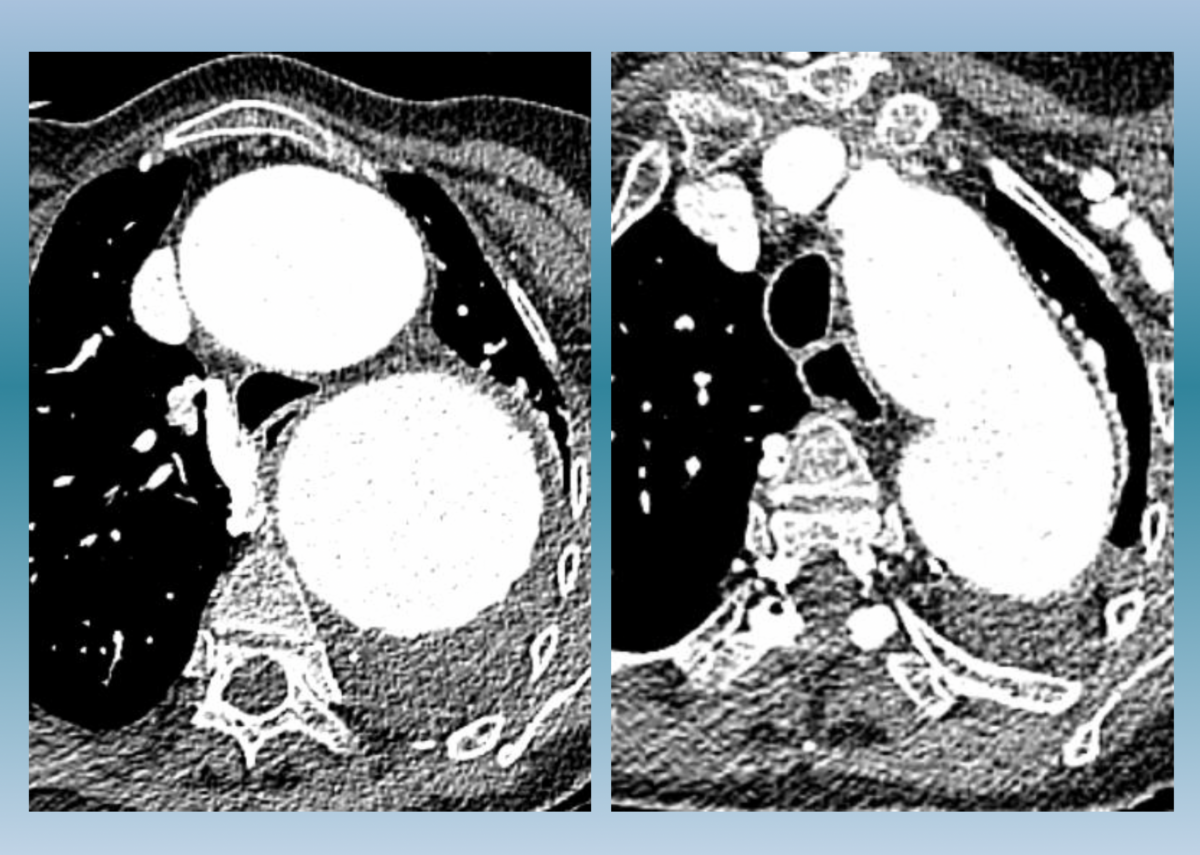

Cancer du poumon

Aggravation progressive d’une difficulté respiratoire chez un patient fragilisé par des infections respiratoires chroniques